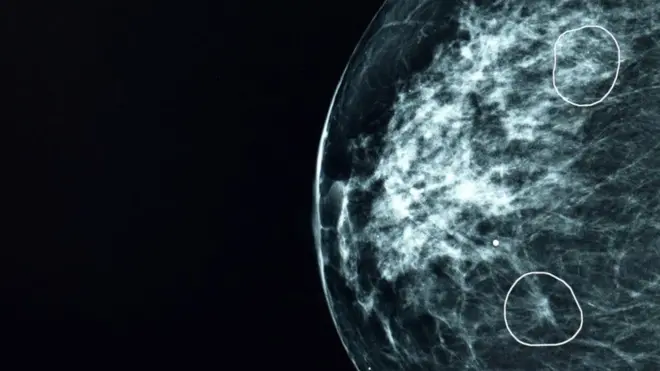

مردی که پس از پیدا شدن یک غده به اندازه نخود متوجه شد که به سرطان پستان مبتلا شده، خواستار کاهش سن غربالگری برای مردان و زنان شده است.

بر اساس آمار مربوط به ابتلای به سرطان پستان در بریتانیا هر ساله حدود ۵۵ هزار زن و ۴۰۰ مرد به این نوع سرطان مبتلا میشوند.

سرطان پستان در مردان نادر است و در بریتانیا، تعداد مبتلایان تنها ۴۰۰ مورد در سال در مقایسه با حدود ۵۵ هزار مورد جدید در زنان است.

غربالگری برای زنان از سن ۵۰ سالگی شروع میشود، اما برای مردان هیچ نوع غربالگری معمول نیست.